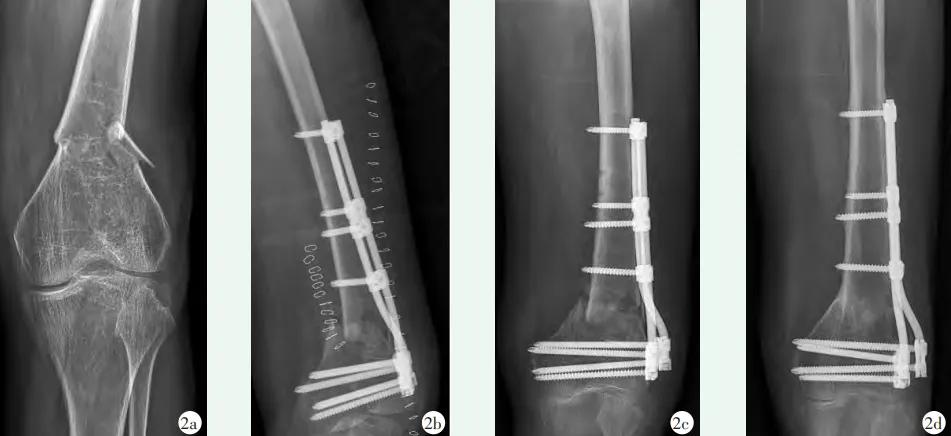

图7 患者,女,65岁,左股骨远端骨折,AO分型C1型,行BCFS双棒固定手术治疗。2a:术前X线示左股骨远端骨折;2b:术后X线片示内固定稳定,内侧皮质重叠;2c:术后1个月X线片示骨折线可见;2d:末次随访X线片提示骨折完全愈合,但存在内翻。